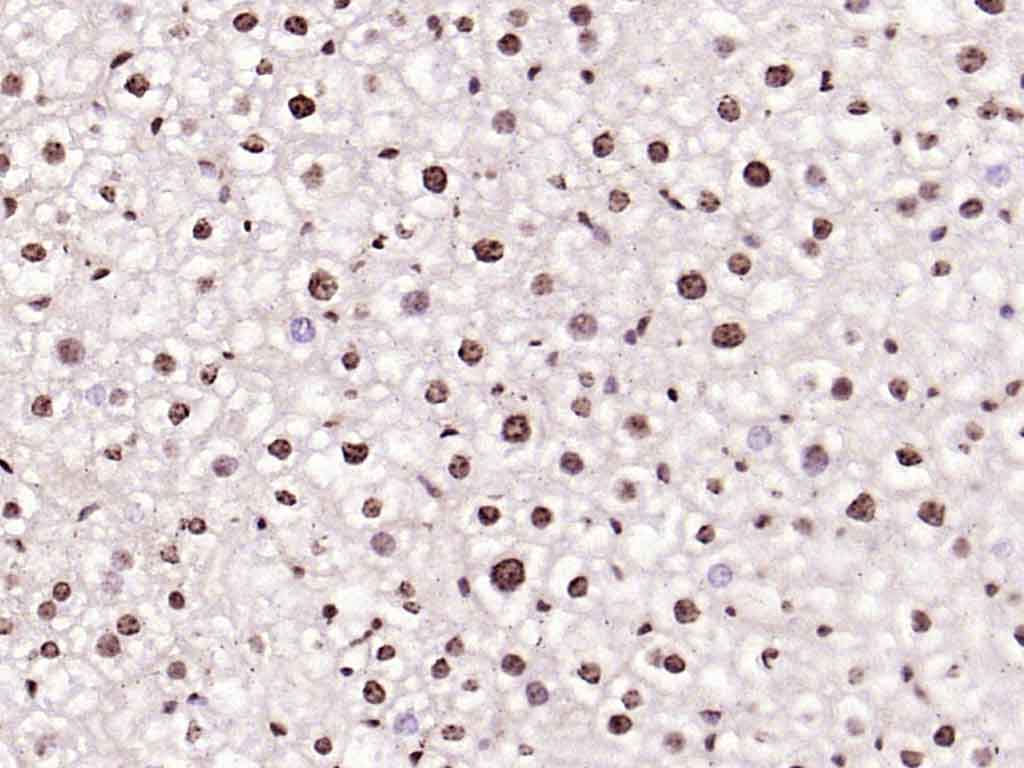

| 英文名称 | phospho-IRS1 (Tyr1229) Rabbit pAb |

| 中文名称 | 磷酸化胰岛素受体底物-1抗体 |

| 产品应用 | IHC-P=1:100-500, IHC-F=1:100-500, ICC/IF=1:100-500, IF=1:100-500, Flow-Cyt=2ug/Test Not yet tested in other applications. |

| 背景资料 | Insulin receptor substrates (IRS) are responsible for several insulin related activities, such as glucose homeostasis, cell growth, cell transformation, apoptosis and insulin signal transduction. Serine/threonine phosphorylation of IRS1 has been demonstrated to be a negative regulator of insulin signaling and is responsible for its degradation, although IRS1 degradation pathways are not well understood. IRS1 has also been shown to be constitutively activated in cancers such as breast cancer, Wilm's tumors, and adrenal cortical carcinomas, thus making IRS1 phosphorylation and subsequent degradation an attractive therapeutic target. To date there have been four subtypes identified: IRS1, 2, 3 and 4, with IRS1 being widely expressed. |

| {IHC-P} | {1:100-500} |